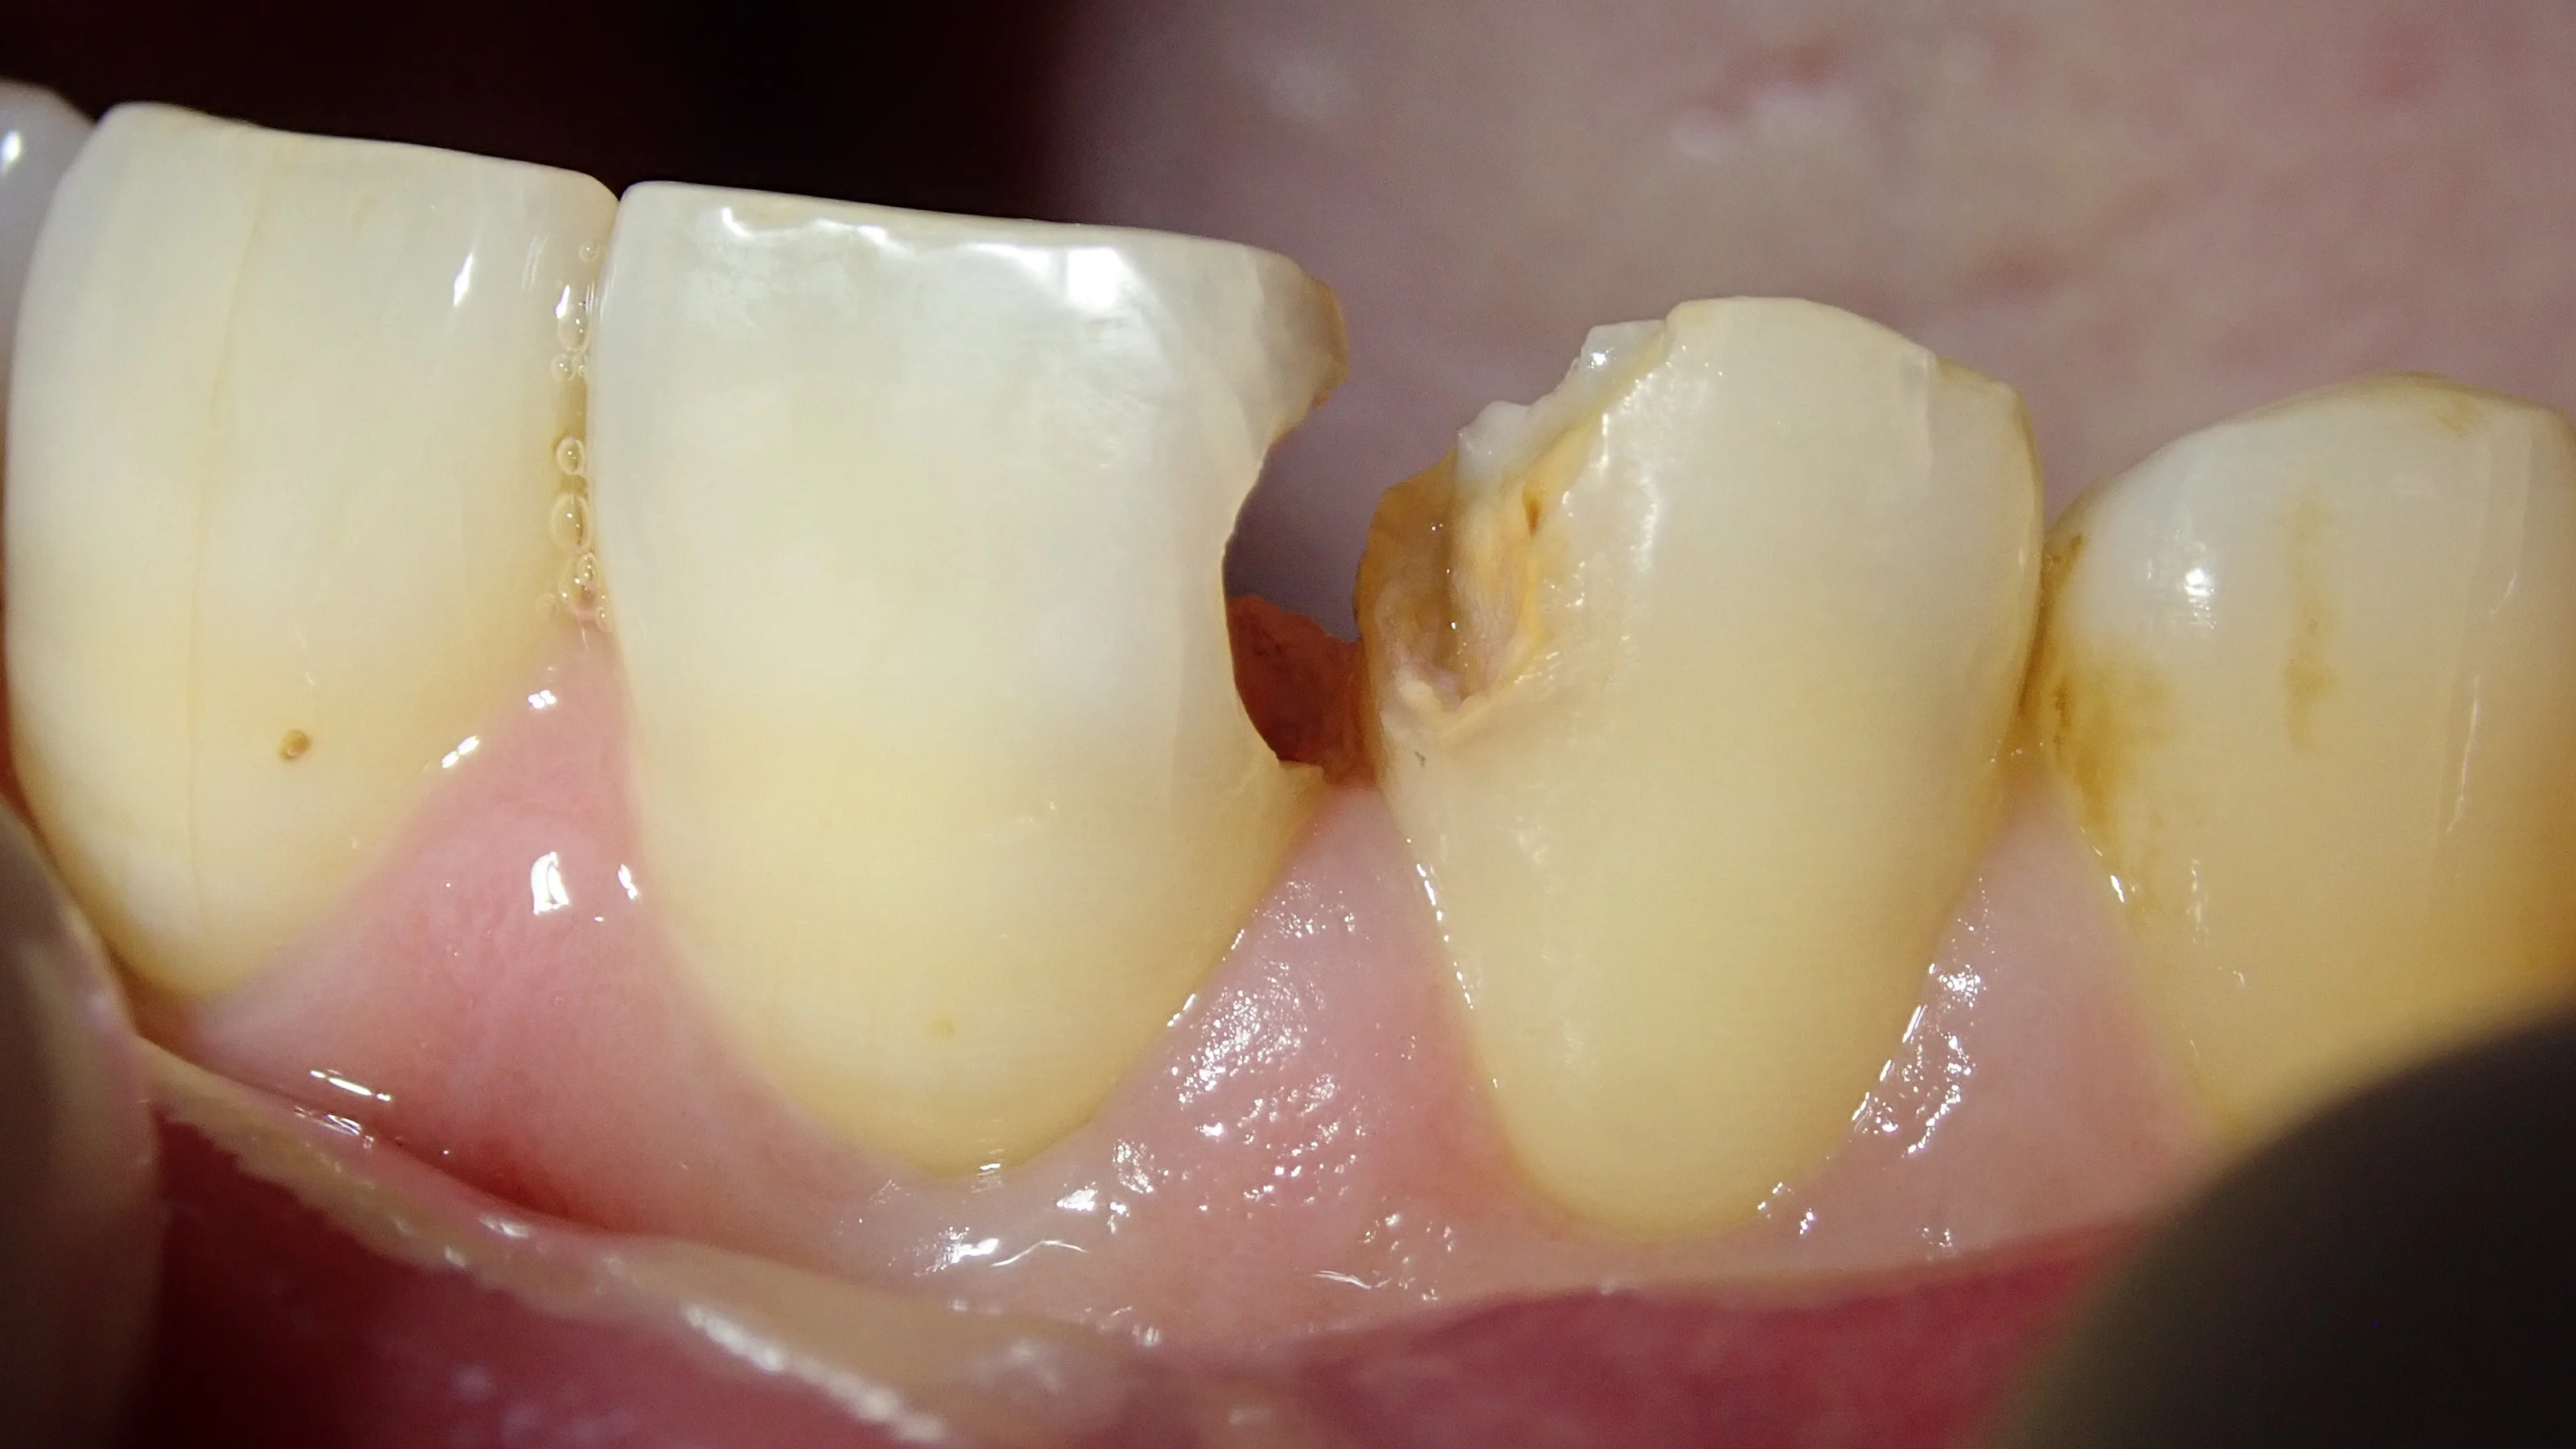

裏側から見た写真がこちらです。

掛けたところの左側にある歯も詰めている部分が黒くなっているのがなんとなくわかるかと思います。